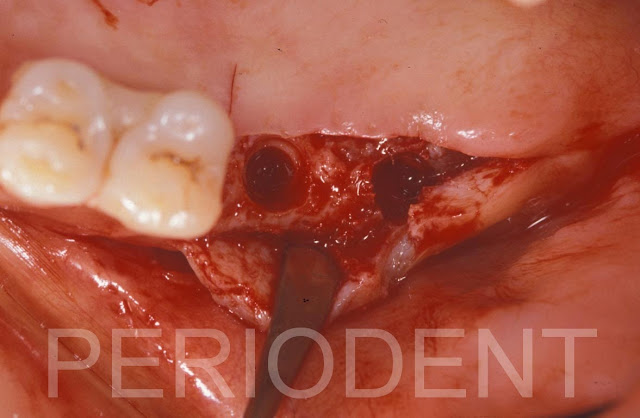

六個月後再度進行鼻竇增高補骨手術及植牙手術,移除原來的不可吸收再生膜

從原有window補骨並覆蓋上原有的不可吸收再生膜